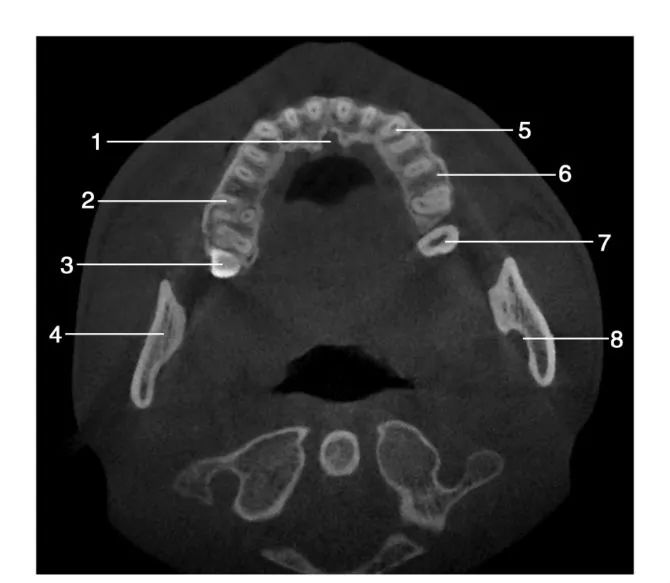

1.切牙孔( incisor foramen) ; 2.右侧上颌第一磨牙( right maxillary first molar) ; 3.右侧上颌第三磨牙( right maxillary third molar) ; 4.下颌支( mandible ramus) ; 5.上颌尖牙( maxillary canine) ; 6.上颌牙槽骨( maxillary alveolar bone) ; 7.左侧上颌第二磨牙( left maxillary second molar) ; 8.下牙槽神经管( inferior alveolar nerve)